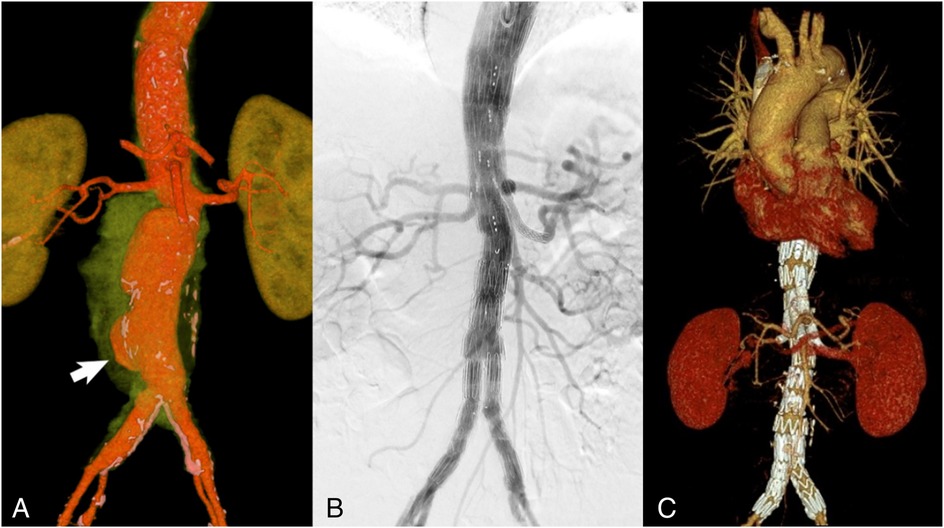

A control CT angiography revealed an increase in the thoracoabdominal aorta diameter to 60 mm × 51 mm with a sac-like bulge at the bifurcation (Figure 4A). Given the high risk of rupture and considering the patient's advanced age and comorbidities, branched endovascular aortic repair (BEVAR) was selected as the treatment strategy.

Figure 4

VRT reconstruction (spatial rendering) (A) CT scan with green-highlighted periaortic pararenal infiltration. The arrow indicates the area of the aortic wall defect and saccular aneurysm formation. Control angiography immediately after BEVAR with an endoprosthesis of all large visceral branches of the aorta (B) and 6 months after surgery (C): all visceral arteries are patent with no signs of endoleaks.

The procedure was performed under general anesthesia with access gained through the left brachial and right common femoral arteries. A branched Zenith t-Branch stent graft (Cook Medical, Bloomington, Indiana, USA) was implanted, followed by selective catheterization and stent grafting of the renal arteries, the superior mesenteric artery (SMA), and the celiac trunk. The final angiography confirmed correct positioning of the device, absence of endoleaks, and preserved perfusion of all visceral arteries (Figure 4B).

Three weeks after discharge, the patient continued chemotherapy for at least 1 year according to the recommended schedule. Six months after surgery, a control CT angiography (Figure 4B) confirmed patency of all visceral arteries, including the renal arteries, the SMA, and the celiac trunk, with no evidence of endoleaks. Para-aortic tissues showed no changes, and areas of destruction in the L2–L4 vertebral bodies had decreased, displaying signs of progressive sclerosis along the margins.